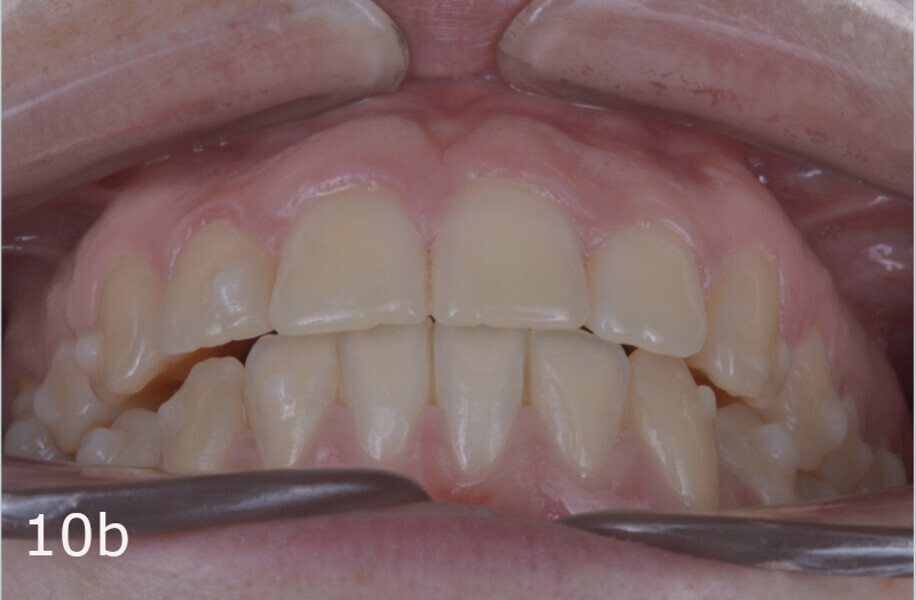

The treatment objectives included closing the anterior open bite, achieving a bilateral Angle Class I relationship and a proper overjet and overbite, correcting the midline discrepancies, and achieving a profile harmonisation. The treatment plan consisted of orthodontic camouflage treatment with asymmetric distalisation in three of the four quadrants using Invisalign aligners (Align Technology) and third molar extraction. The Invisalign Comprehensive package was chosen, and 63 pairs of aligners were used (Figs. 7–10). Each aligner was worn for 20 hours a day for one week each. The use of Class III elastics on both sides was indicated. Afterwards, ten refinement aligners were needed to improve the interdigitation on the right side (Figs. 11 & 12).

The total treatment time was 15 months. An Angle Class I relationship was established along with adequate anterior and canine guidance, establishing a functional occlusion. This not only ensures optimal masticatory function but also protects the teeth and the temporomandibular joint from excessive force. Maxillary and mandibular fixed retention were installed at the end of the treatment (Figs. 13–19).